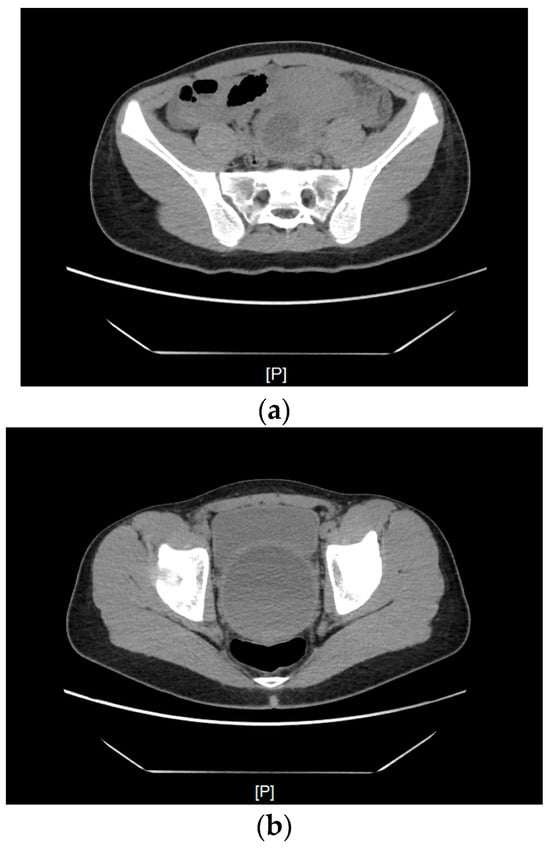

The patient was admitted to the Department of Pediatric Surgery and Urology. Before the hymenotomy, the patient underwent computed tomography (CT), which showed a significantly distended vagina filled with blood measuring approximately 78 mm × 81 mm × 130 mm. The uterus was elevated superiorly, with fluid present in the uterine cavity—features typical of hematometra. Enlarged parametrial venous plexuses were observed, along with edema of the adipose tissue along the parametrial ligaments (Figure 1).

Figure 1.

A CT scan of the uterus elevated superiorly, with fluid present in the uterine cavity, modeling the urinary bladder and rectum. (a) A scan at the level of the promontory. (b) From the superior part of the scan (anteroposterior): the urinary bladder, the uterus filled with hyperdense fluid, and posterior to it, the compressed rectum. (c) A scan at the level of the pubic symphysis. (d) A scan below the greater trochanter of the femur—a visibly enlarged vagina.